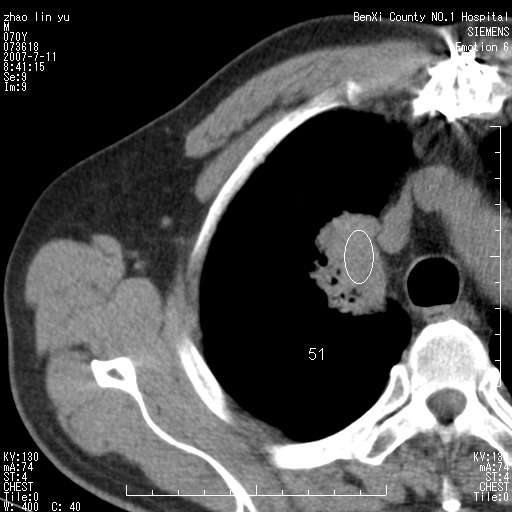

以下是引用王靖旗在2007-7-10 17:12:00的发言:[br] 男、70、咳嗽两个月,半年前换瓣手术,胸片未见异常,于昨天行x片发现右肺上野大片影,行ct扫描,这里是减薄图像,余肺正常。明天晚上会有增强扫描片,到时我会上传。[br][br] 冠状位请大家细看,应该是有意义的,[br][br] 请大家先看平扫发表意见。[br][br]

以下是引用zhangzhongshou在2007-7-10 21:43:00的发言:[br]右肺上叶周围型肺癌,以孤立型细支气管肺泡癌可能性大。